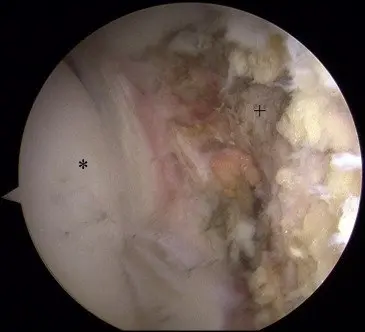

A diagnostic arthroscopy is performed, switching portals frequently to access all parts of the joint. Any additional pathology in the joint is addressed before LT reconstruction. The LT is examined and probed upon identification of a complete tear (Fig 1 and Video 1); the stump in the acetabular fossa is cleared with the Nav X ablation device (Arthrex, Naples, FL) and a shaver (Fig 2).

Fig 2. Arthroscopic view of left hip after debridement of LT stump from fossa. The patient is in the supine position, with visualization of the central compartment of the hip through the anterolateral portal. (Asterisk, femoral head; plus sign, fossa.)